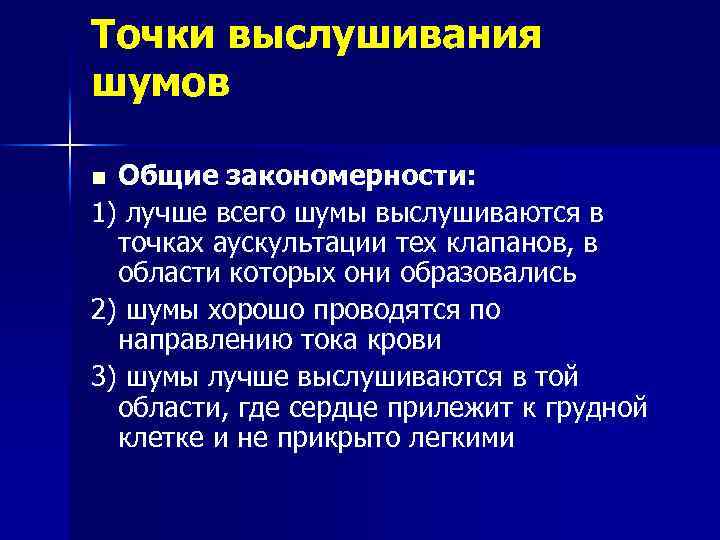

Точки выслушивания шумов Общие закономерности: 1) лучше всего шумы выслушиваются в точках аускультации тех клапанов, в области которых они образовались 2) шумы хорошо проводятся по направлению тока крови 3) шумы лучше выслушиваются в той области, где сердце прилежит к грудной клетке и не прикрыто легкими n